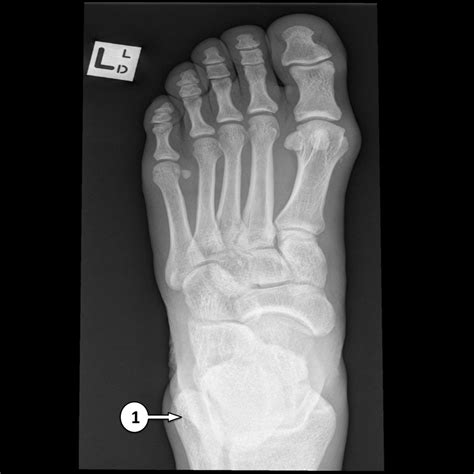

In a normal Xray, the bones should appear smooth and continuous, with no visible fractures or dislocations. The joint spaces should be uniform, and there should be no signs of bone spurs or other abnormalities.

Anteroposterior (AP) View Shows the front of the foot, including the toes, metatarsals, and tarsal bones.

• left foot x ray